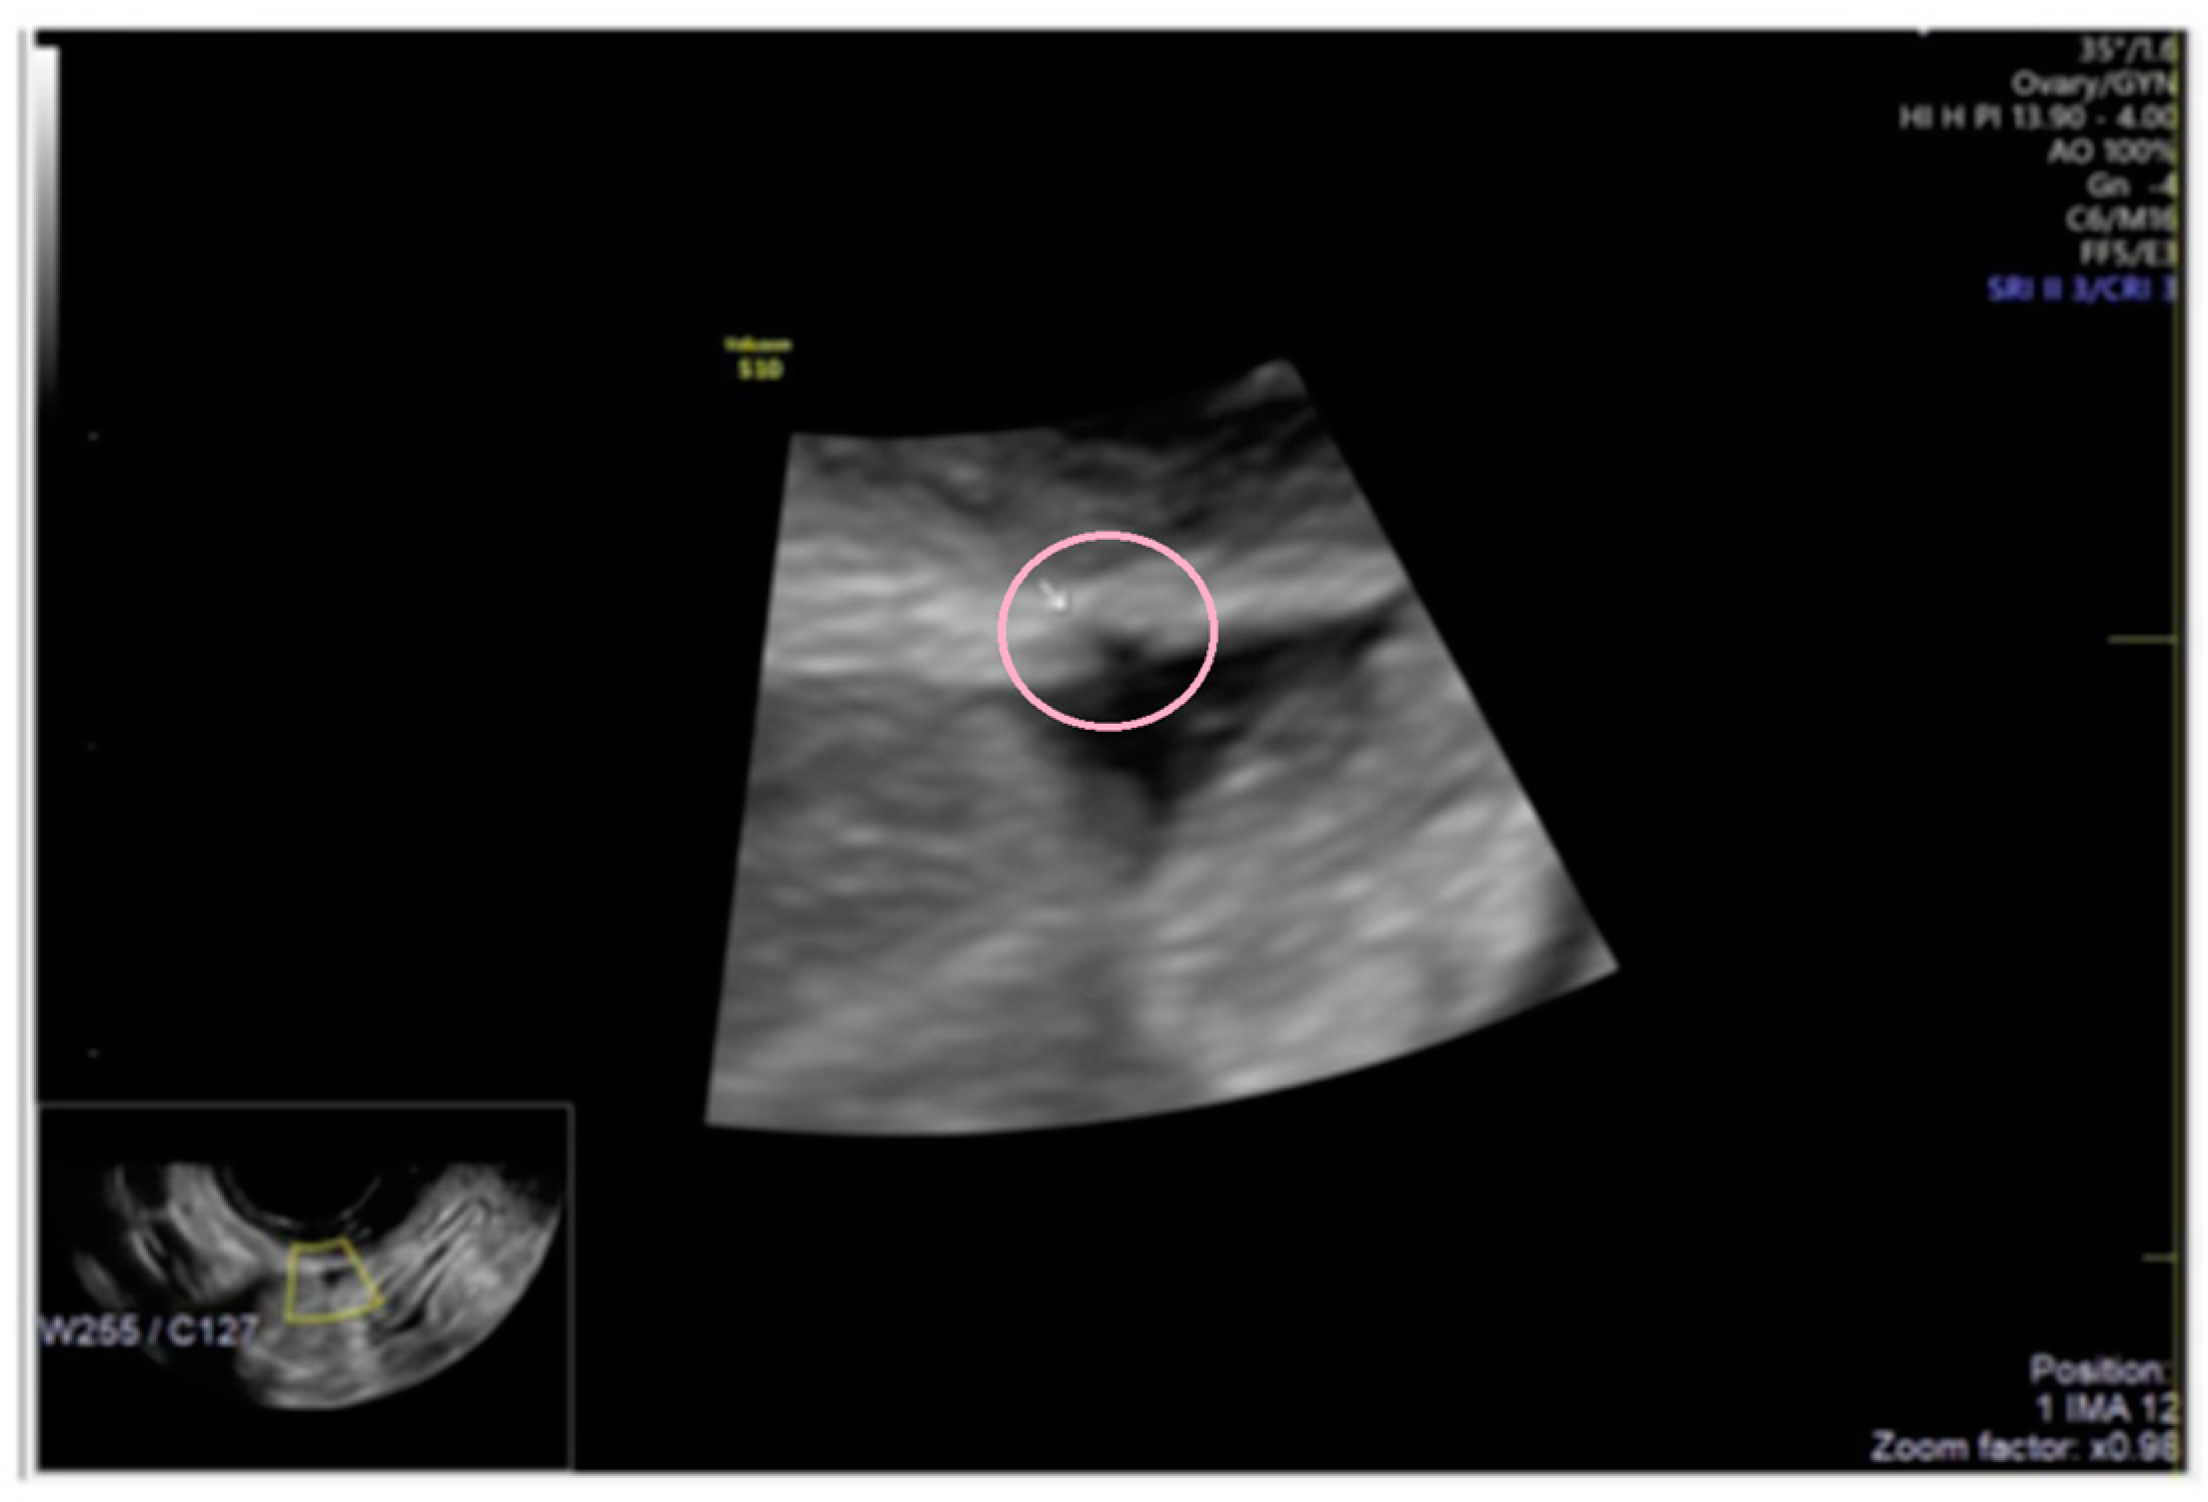

3.2. Cystic Multiple Separate Lesions

3.3. Cystic Lesions Arranged in a Cluster